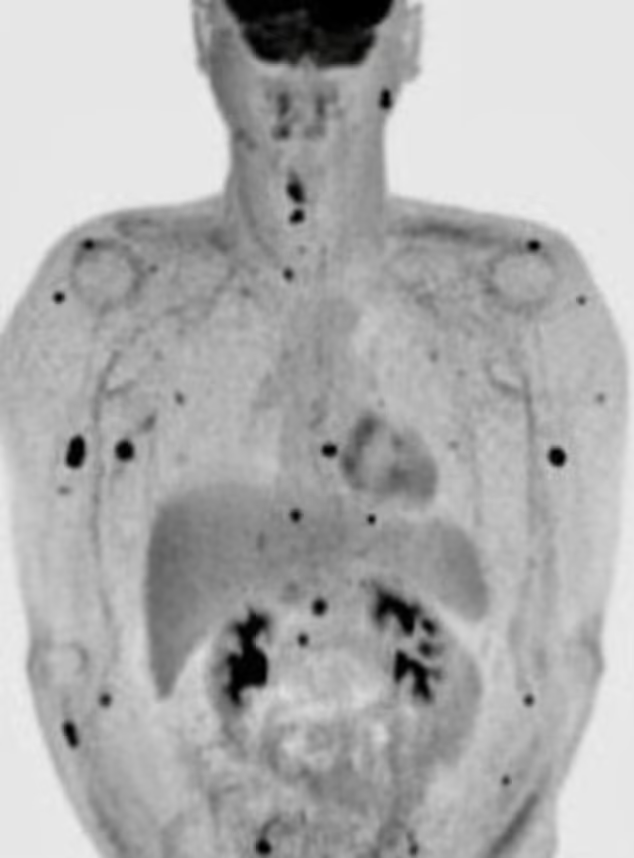

It was only after going through a PET scan that he learned that his cancer had spread throughout his body and he could no longer hope for a cure.

His cancer, unfortunately, spread and he was given a prognosis of 6 months by the doctors. Credit: Daily Mail.

Doctors gave him six months to live in August.